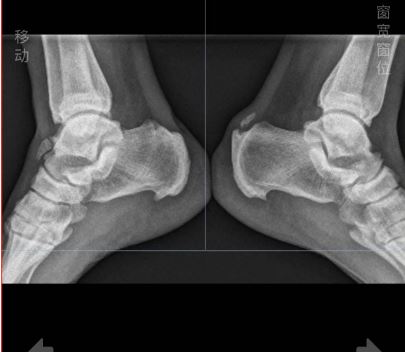

跟腱钙化是肌腱钙盐沉积导致,钙化的跟腱在X光下会表现为高亮度,和骨骼的亮度是相接近的。如果患者长时间进行剧烈运动,或进行繁重体力劳动等,都容易反复牵拉跟腱部位的胶原纤维,从而引起局部组织韧带损伤,出现跟腱钙化。在出现跟腱钙化后,可能表现为不能长时间站立、走路疼痛、跟腱水肿等症状

还有一种跟骨形态畸形:Haglund综合征—Haglund病是指跟骨后上部异常突起,跟骨后上方和跟腱之间的滑囊在反复的机械撞击下产生的炎性症状。 这种情况下保守治疗无效也应该手术治疗,磨除骨刺。